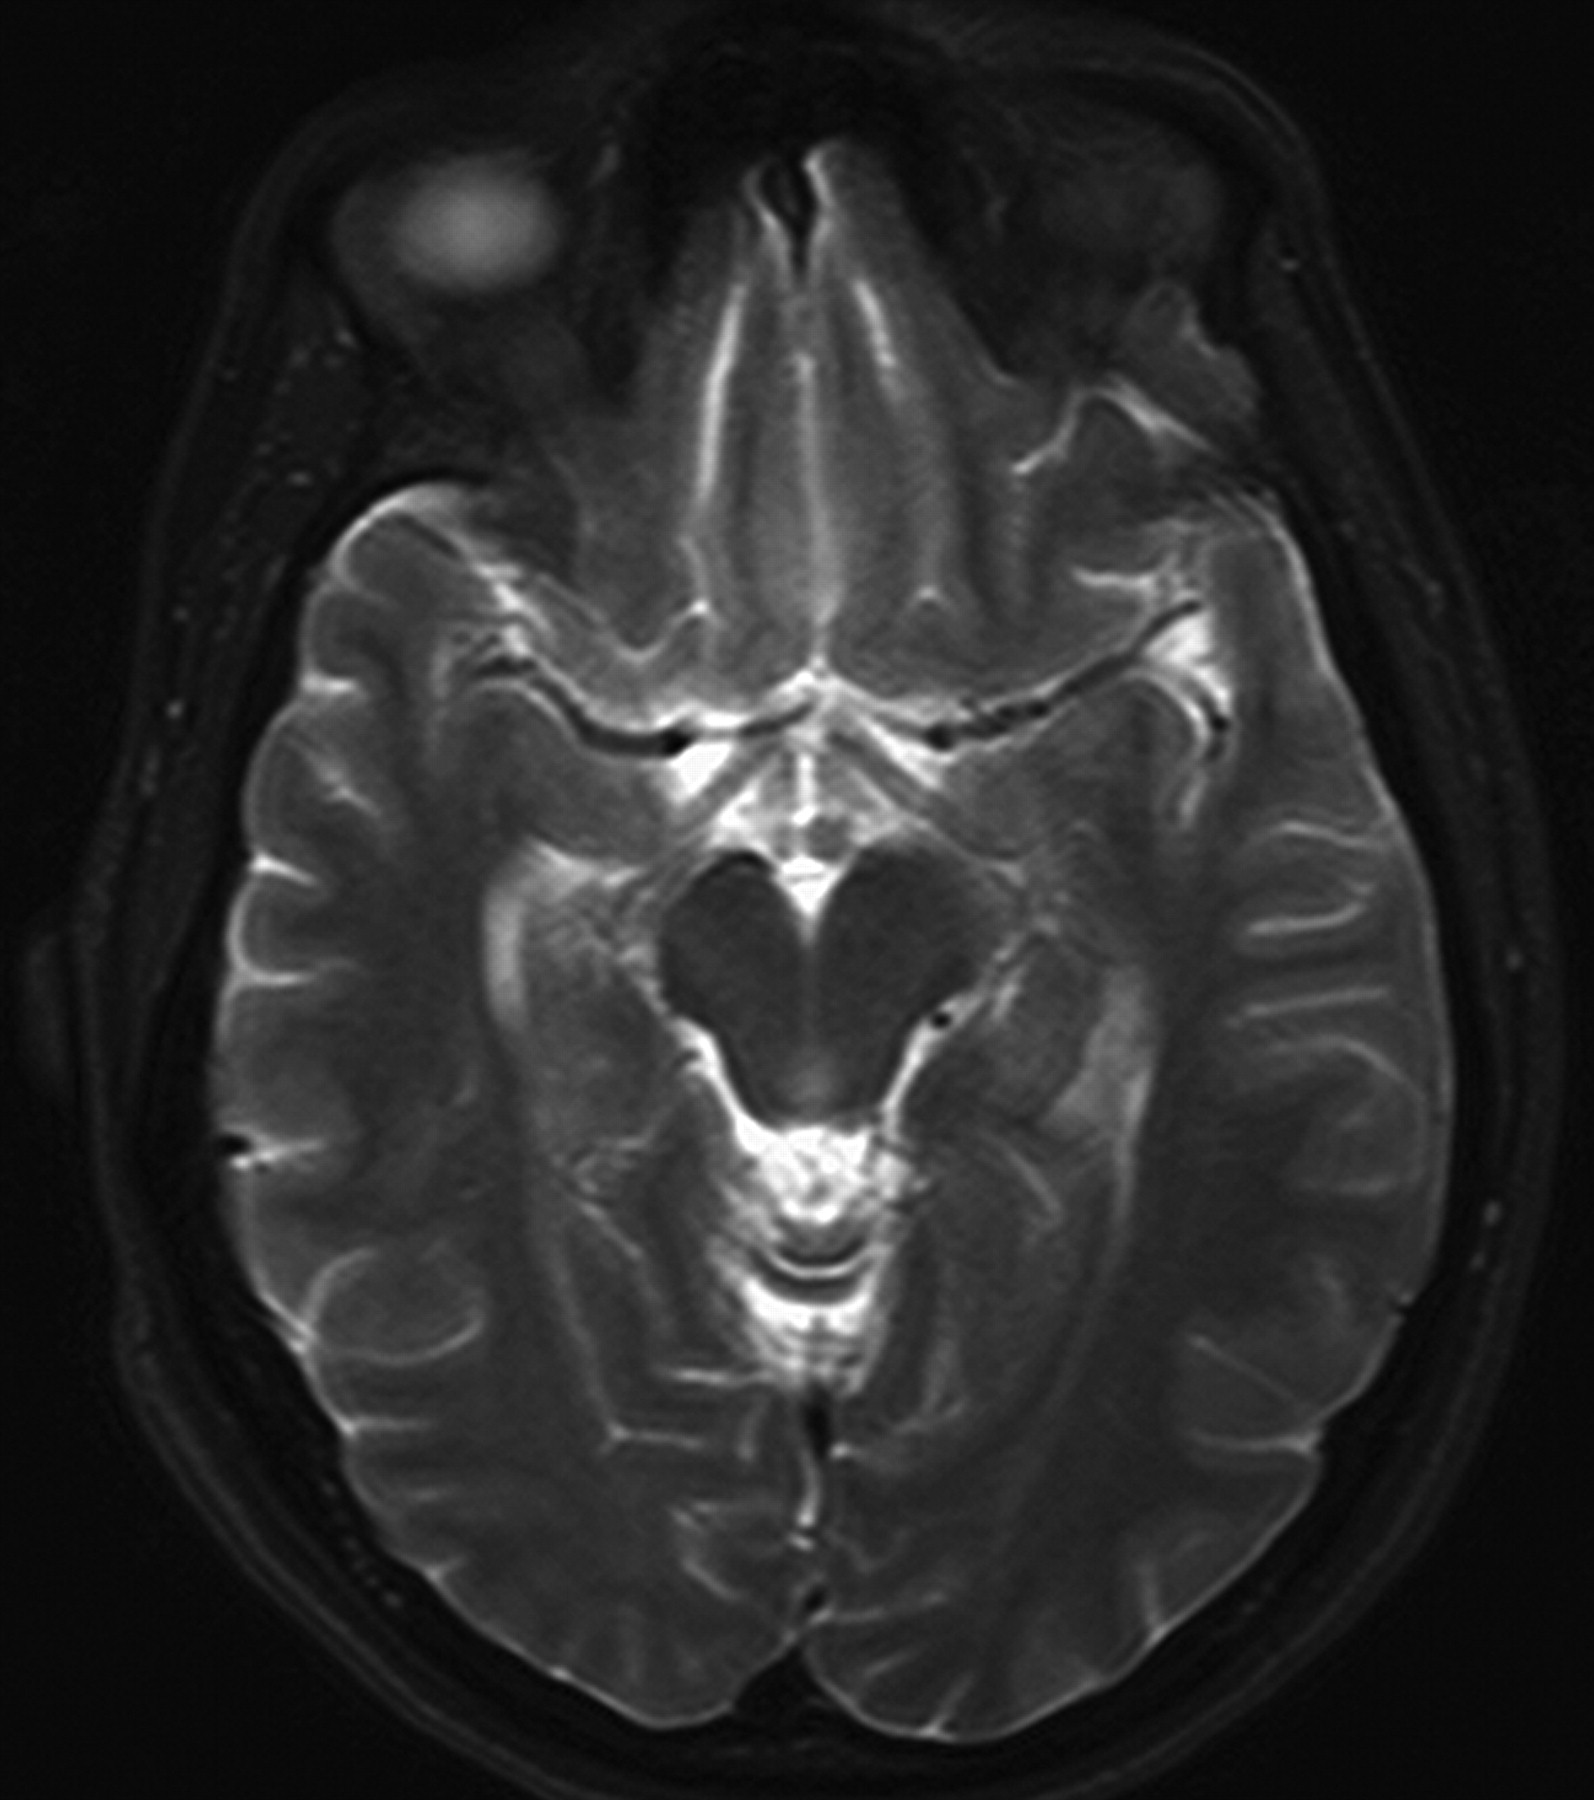

Mamillary body volume loss and MTS. The axial T2-weighted (TR/TE/TI, 4,000/98/1) image at the level of the mamillary bodies reveals a smaller mamillary body on the side of the hippocampal sclerosis.